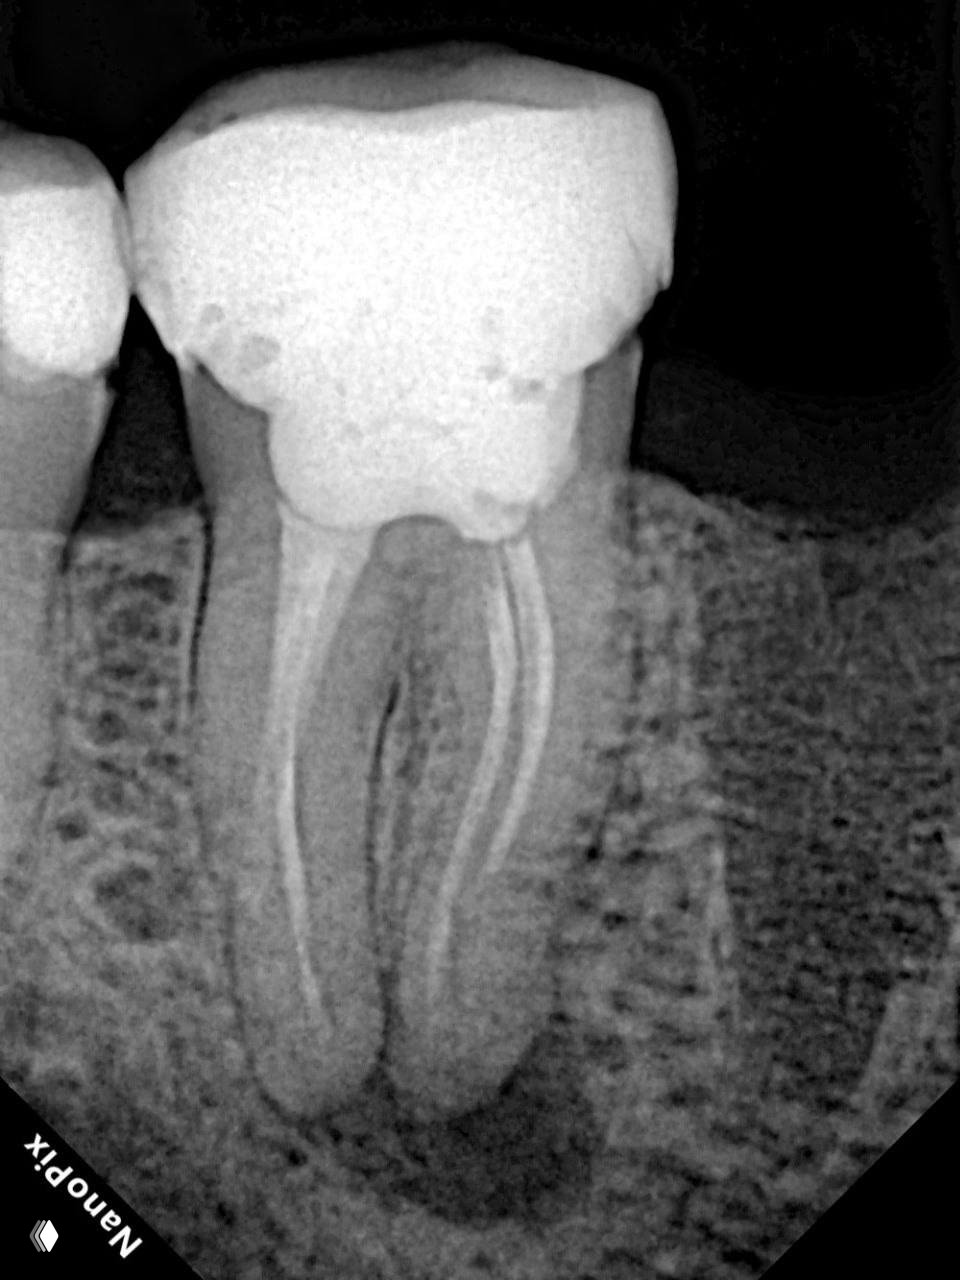

Клинический разбор: перфорация закрыта МТА, но боль сохранялась — причина в негомогенной обтурации и потребовалось перелечивание с разными методиками обтурации.